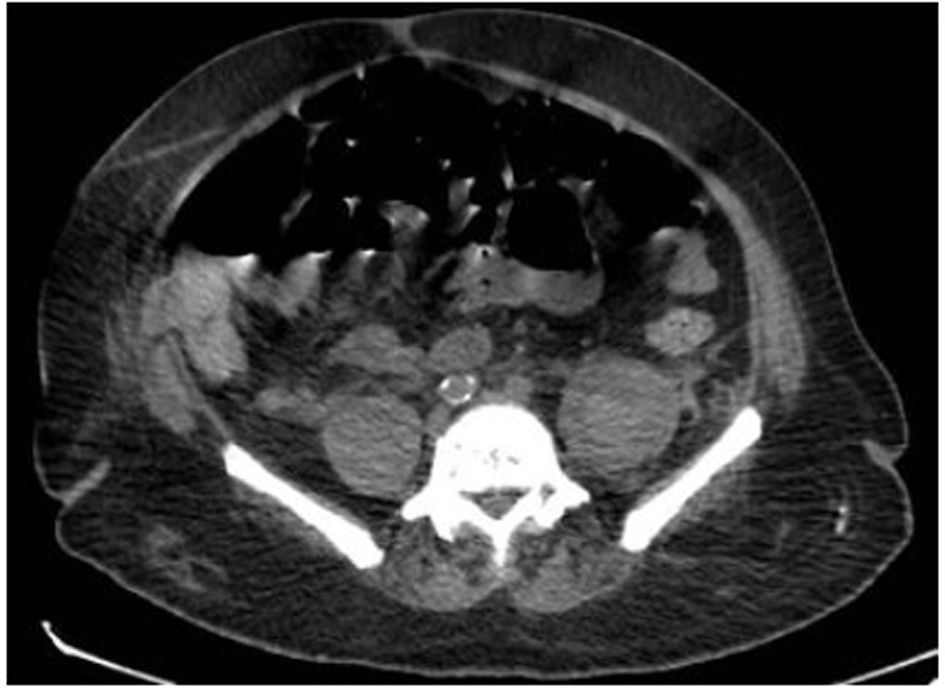

After that, non-enhanced abdomen and pelvis CT scan was performed and showed heterogeneous organized collections identified along the right and left psoas muscles causing focal contour bulge representing hematoma, with the volume reaching approximately up to 100 mL on the right side and 150 mL on the left side. There is minimal fat stranding surrounding the psoas muscles, more significant on the left side (Fig. 3, 4).

![]() Click for large image | Figure 4. There are heterogeneous organized collections identified along the right and left psoas muscles causing focal contour bulge representing hematoma, minimal fat stranding surrounding the psoas muscles, more significant on the left side. |